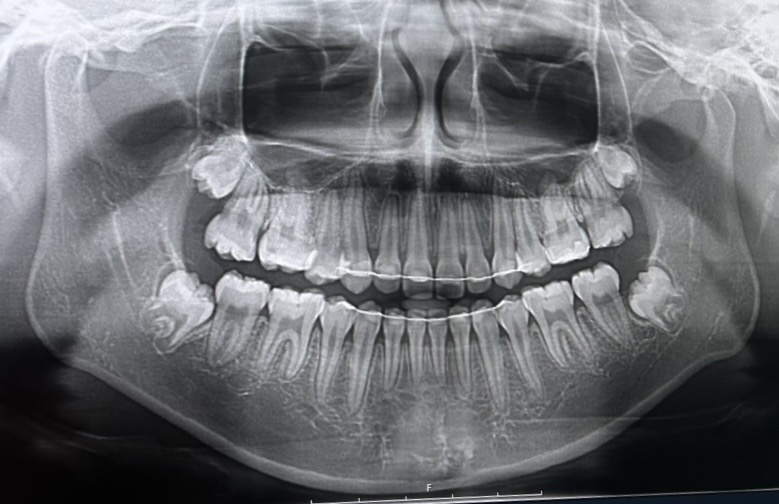

신경선 낮은지좀 봐주라ㅠㅠ 그리고 광대도 깎으면 효과 있을거같아? 사각턱도 많이 자를 수 있으려나